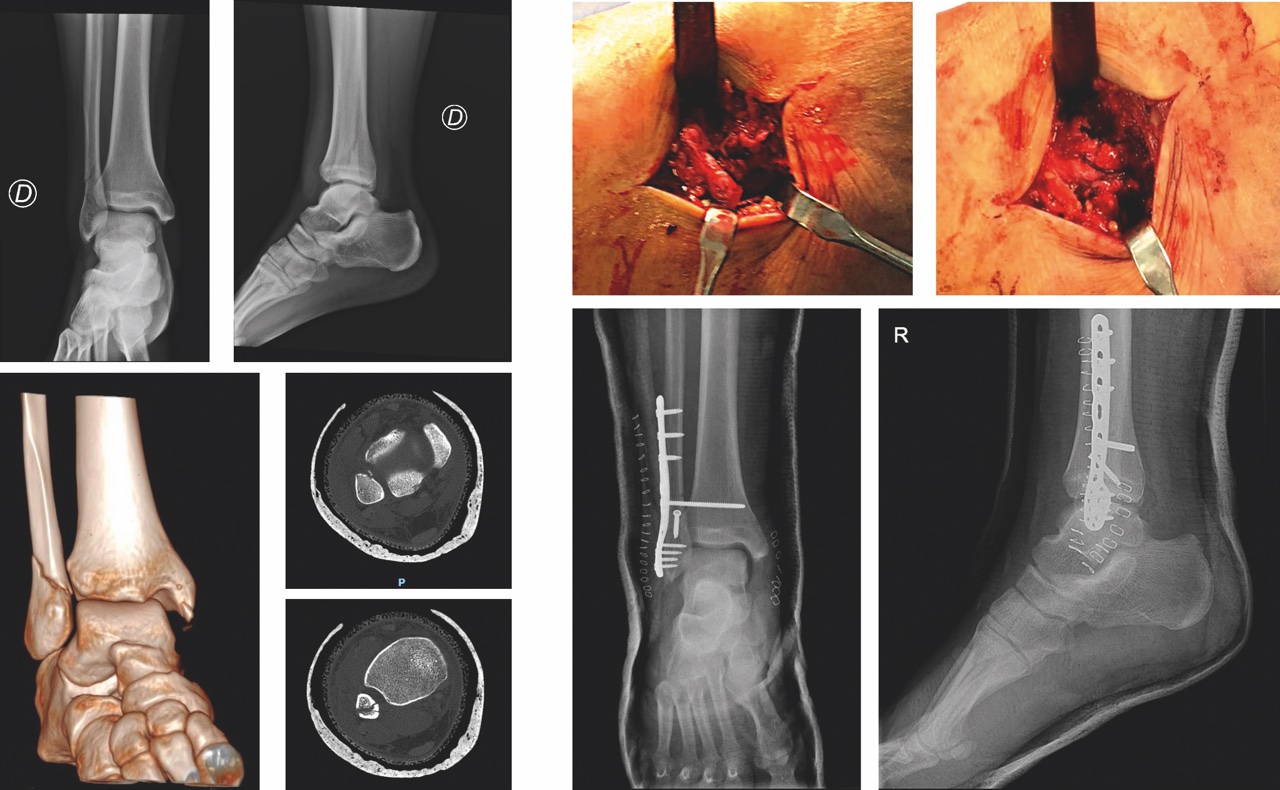

Inoltre, nelle lesioni stabili e nelle fratture isolate composte del malleolo laterale vanno sempre ricercate lesioni del legamento deltoideo e della sindesmosi (Fig. 3). La stabilità della caviglia deve essere valutata con caute manovre in varo-valgo e in rotazione esterna. Un’instabilità anteriore dell’astragalo (test del cassetto anteriore) è indice di una lesione traumatica legamentosa, mentre una contrattura dei muscoli peroneali può celare un’instabilità laterale. Infine va esaminato lo stato neuro-vascolare con particolare attenzione alle paralisi complete o parziali del nervo peroneo comune. Lo studio di imaging prevede tre proiezioni radiografiche (AP standard, mortise view e la proiezione laterale) e permette di valutare l’angolo tibio-astragalico (v.n. 83° +/- 4°) che qualora risultasse maggiore o minore deporrebbe per un quadro di instabilità, cambiamento della lunghezza del perone o lussazione del mortaio TPA. La Tomografia Computerizzata è necessaria per una corretta pianificazione dell’intervento chirurgico e allo stesso tempo per identificare la presenza di una frattura del pilone tibiale, del tubercolo di Le Fort, del tubercolo di Chaput e del triangolo di Volkmann.

Il trattamento delle fratture malleolari sia esso conservativo o chirurgico, è fortemente condizionato dallo stato dei tessuti molli (considerare per questo motivo l’utilizzo di un FEA temporaneo), dall’obesità e nel paziente anziano anche dall’osteoporosi e da un’eventuale politerapia farmacologica. Le fratture infrasindesmosiche isolate del malleolo peroneale e stabili, possono essere trattate incruentemente. L’indicazione può divenire chirurgica in relazione all’instabilità e all’ incongruenza del mortaio in quanto tali fratture, provocando un carico anomalo sulla superficie articolare, possono portare a un quadro di artrosi precoce. La ricostruzione del perone, finalizzata al ripristino dell’asse e della corretta lunghezza, è il primo step durante l’osteosintesi delle fratture malleolari; l’utilizzo delle placche di ultima generazione, anche ad esempio con funzione di sostegno, associata a vite interframmentaria nel trattamento delle lesioni di tipo B con frattura di perone a rima obliqua corta, permette di non compromettere la vascolarizzazione periostale e raggiungere anche ad esempio in un paziente anziano un corretto bone healing. In caso però di frammento da strappo del malleolo laterale, così come nelle fratture da avulsione del malleolo tibiale (di solito in quelle di tipo B), può essere eseguita una sintesi con tirante secondo Weber. Sempre nelle fratture tipo con frattura isolata del malleolo peroneale una possibile insufficienza del legamento deltoideo è meglio diagnosticata con radiografie sotto stress o con Rx di controllo dopo 1 settimana dal trauma.

Il distacco del malleolo posteriore (nelle Tipo B), invece, può invece essere ridotto indirettamente trattando il malleolo laterale, laddove però tale frammento sia riconducibile a un tipo I secondo la classificazione TAC di Bartonıcek and Rammelt7. La raccomandazione che emerge oggi dall’analisi della letteratura è la necessità di trattare chirurgicamente il terzo malleolo allorquando il frammento sia di grandi dimensioni e coinvolge la superficie articolare: la sintesi deve ovviamente essere stabile ed eseguita a cielo aperto attraverso l’accesso postero-laterale 8.

Nelle fratture sovra-sindesmosiche (tipo C) va considerato sempre l’utilizzo di una vite di stabilizzazione della sindesmosi posizionata con piede in lieve flessione dorsale per impedire il restringimento del mortaio. Secondo la nostra esperienza, nelle fratture da fragilità, è preferibile eseguire una stabilizzazione della sindesmosi quadricorticale allorquando non venga utilizzata una fissazione dinamica poiché, in caso di rottura del mezzo di sintesi, è possibile rimuovere il frammento filettato mediante un accesso dalla corticale tibiale mediale. La fissazione statica della sindesmosi deve essere eseguita a 2 cm prossimalmente all’articolazione introducendo le viti (possibilmente due, da spongiosa 4 mm) obliquamente dalla parte posteriore a quella anteriore con un angolo di 25°-30°. La presenza di un Hook test positivo e l’allargamento dello spazio articolare visibile con scopie intraoperatorie maggiore di 2 mm indicano un’instabilità della sindesmosi e pertanto l’obbligatorietà al trattamento chirurgico.